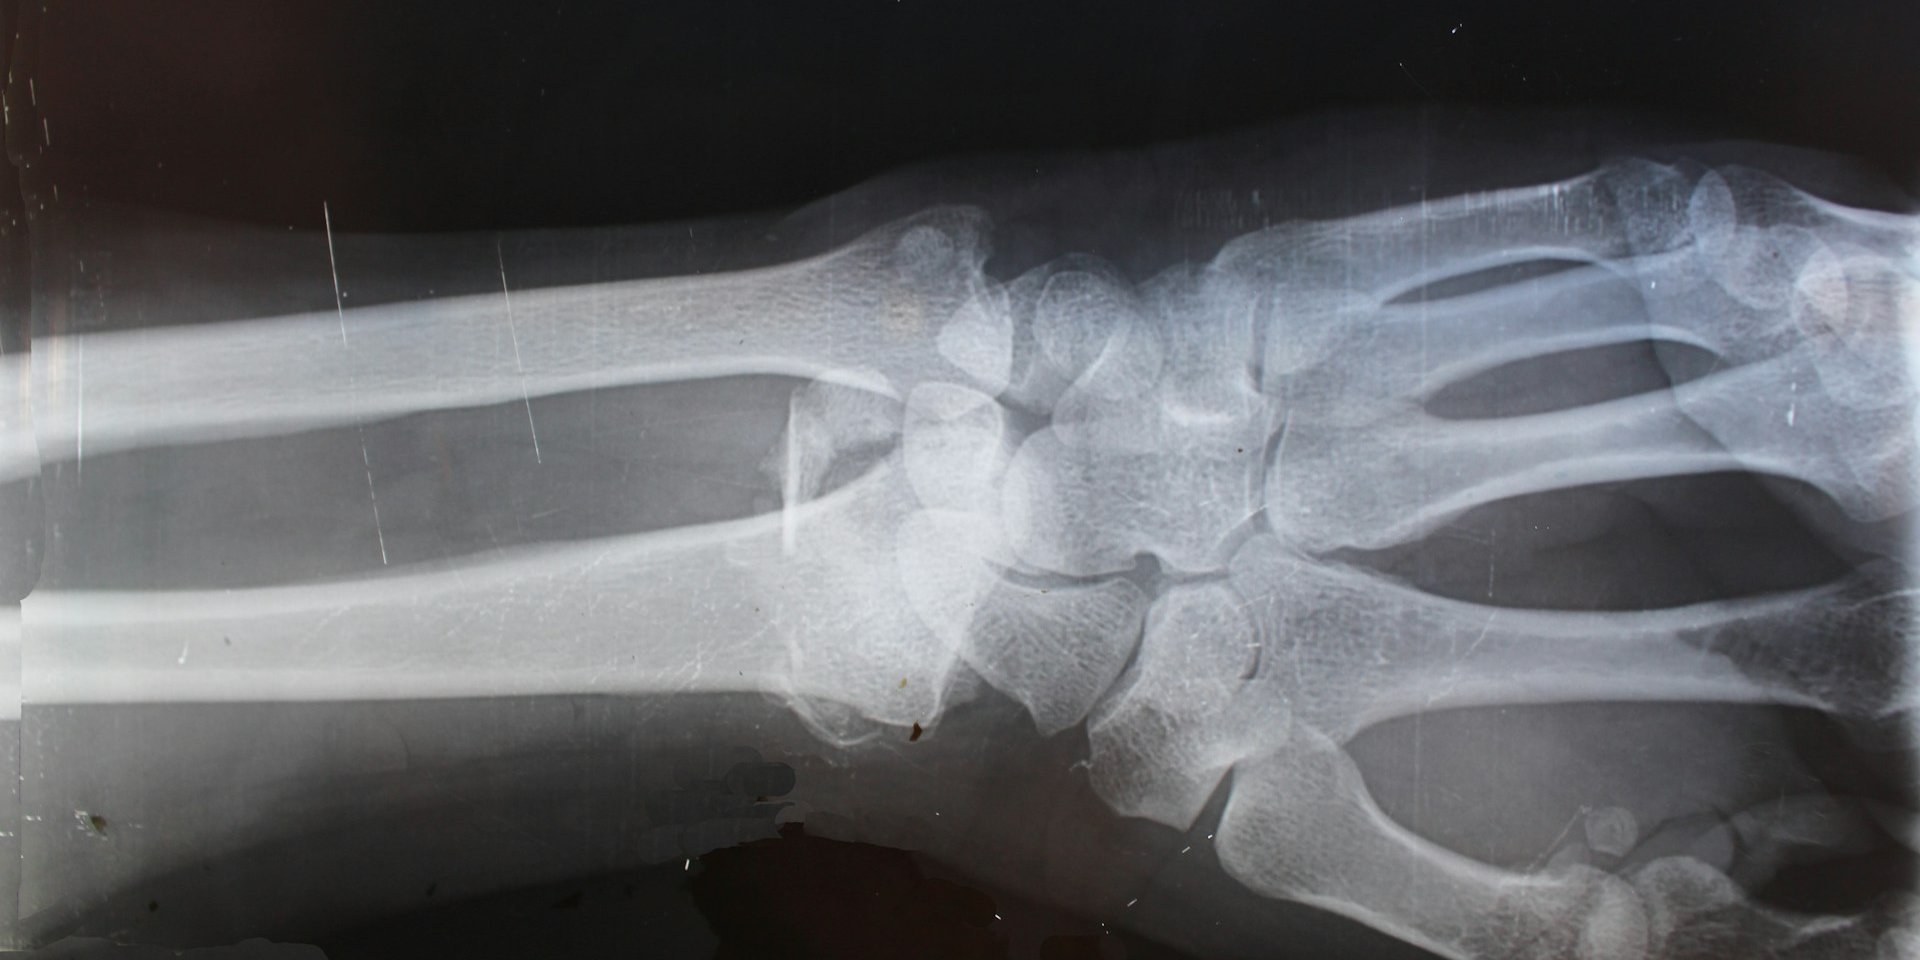

Исследователи из Швейцарской высшей технической школы Цюриха (ETH Zurich) разработали инновационный гидрогель, который может в корне изменить подход к лечению сложных переломов и удалению костных опухолей.